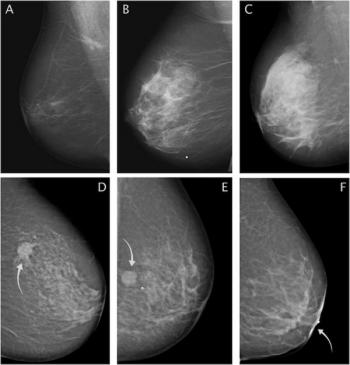

In a large retrospective study involving over 523,000 digital breast tomosynthesis (DBT) exams and over one million digital mammography (DM) exams, researchers found that DBT was associated with significantly lower recall rates but showed no advantage over DM in the diagnosis of interval or advanced breast cancer.

Six reader studies on digital mammography revealed a pooled sensitivity rate of 80.8 percent for stand-alone artificial intelligence (AI) in comparison to 72.4 percent for radiologist assessment while seven historic cohort studies showed a 75.8 percent pooled sensitivity rate for stand-alone AI versus 72.6 percent for radiologist interpretation of digital mammography.